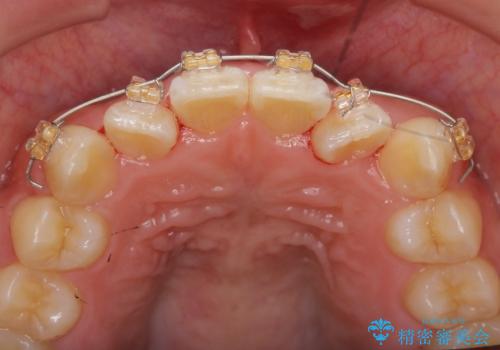

マウスピース矯正では改善の難しい前歯のねじれを前歯の部分ワイヤー矯正で改善したのち、インビザライン矯正を行い歯列を整えます。

インビザラインを行う前に前歯の部分矯正を行ったことで、しっかりとねじれが取れ整った歯列へと仕上げることが出来ました。